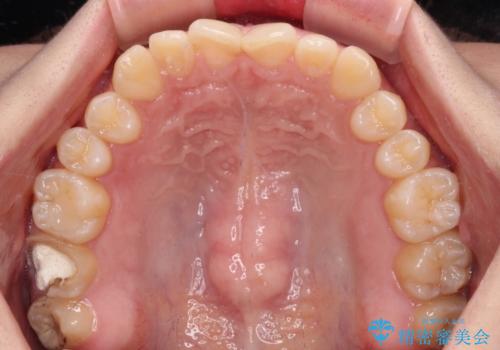

治療途中の奥歯と矯正治療の後戻り インビザライン・ライトによる矯正治療

- 根管治療を行ったままの奥歯と、矯正治療の後戻りを気にして来院された患者様です。

根管治療された歯に症状はなく、オールセラミッククラウンにて補綴治療を行うこととしました。

矯正治療の後戻りは軽微であったため、インビザラインの簡易パッケージであるインビザライン・ライトを用いて歯列を整えることとしました。

クラウンはよりよい咬み合わせで装着したいため、インビザラインを1セット使用して概ね歯列を整えた時点で補綴治療を行い、その後仕上げの矯正治療を行いました。